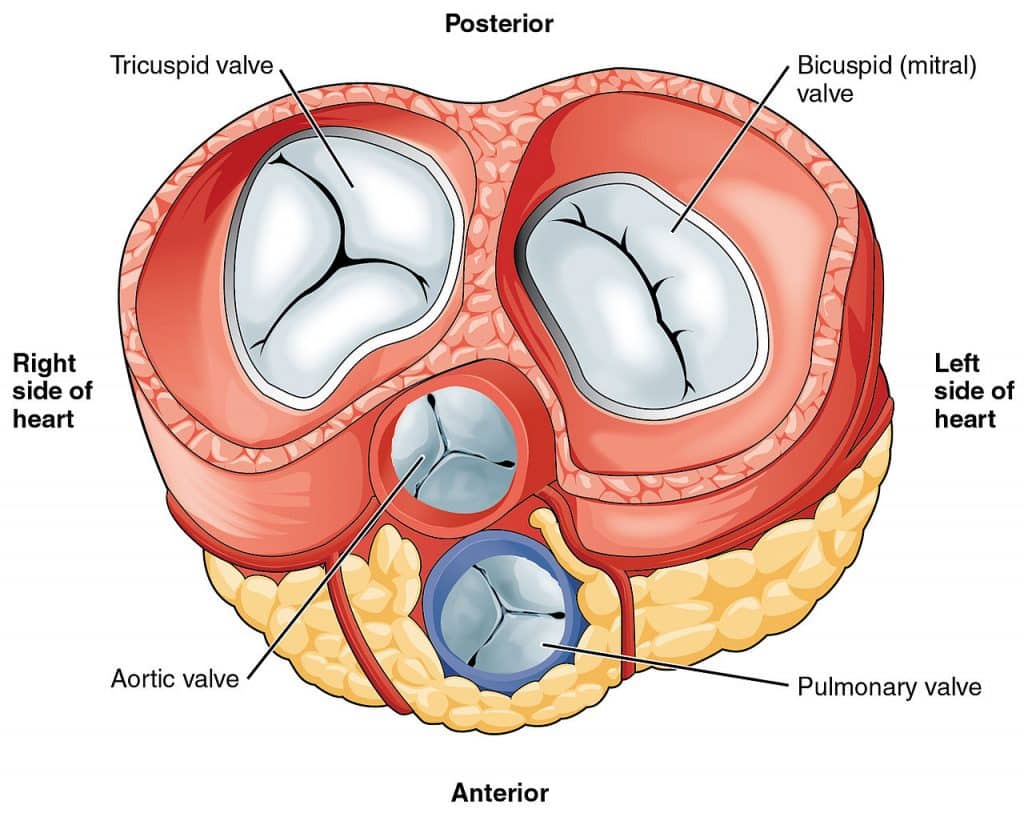

The tricuspid valve consists of three flaps or leaflets however cases are found when the tricuspid valve consists of only two or even four leaflets instead of the traditional three. The tricuspid valve lies within the right trigone.

Tricuspid valve anatomy. An appreciation of the complex and variable anatomy of the tricuspid valve is essential to unraveling the pathophysiology of tricuspid regurgitation. It is the atrioventricular valve that allows blood to flow from the right atrium to the right ventricle. Then blood exits the heart via the pulmonary artery.

Anatomy of the tricuspid valve. The tricuspid valve complex consists of the annulus leaflets right ventricle papillary muscles and chordae tendinae. Right atrioventricular valve tricuspid valve these are large veins that transport deoxygenated blood from the body back to the heart.

The valve has anterior posterior and septal leaflets cusps the bases of which attached around the av orifice to the fibrous ring fibrous skeleton of the heart. Blood collects within the right atrium and it must flow through the tricuspid valve in order to enter the right ventricle. The tricuspid valve functions as a one way valve that closes during ventricular systole to prevent regurgitation of blood from the right ventricle back into the right atrium.